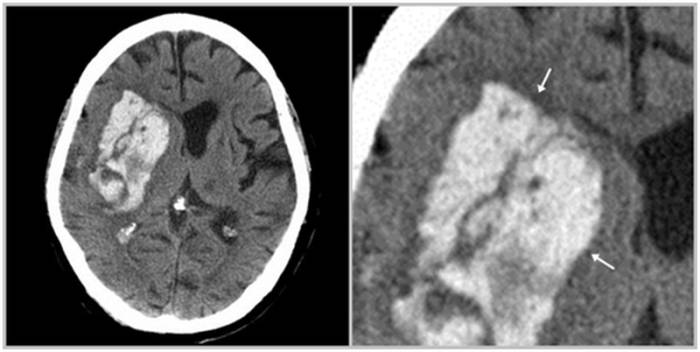

В медицинской практике выделяют несколько видов внутричерепных кровоизлияний:

• Интрапаренхиматозная гематома — возникает из-за разрыва сосудов при геморрагическом инсульте, чаще всего из-за повышенного артериального давления, травмы артерии или воспалительных процессов. На снимках кровоизлияние расположено среди белого вещества мозга, не связанное с повреждением костей черепа, даже если возникло после удара головы.

• Субарахноидальное кровоизлияние (САК) — происходит из-за разрыва сосуда на поверхности мозга в подпаутинном пространстве, например, при разрыве мешотчатой аневризмы. Основные симптомы: внезапная сильная головная боль, тошнота с рвотой, светобоязнь и угнетение сознания до комы. САК может вызывать вазоспазм и на снимках располагается на поверхности мозга.

• Субдуральная гематома — локализуется под твердой мозговой оболочкой и имеет форму серпа на магнитно-резонансной или компьютерной томографии. Возникает из-за разрыва вен после травм, приема антикоагулянтов или шунтирования желудочков, характеризуется высоким уровнем летальности и вызывает смещение мозга из-за внутричерепного давления.

• Эпидуральная гематома — обычно возникает после травматических повреждений. Локализуется под областью перелома, между костями черепа и твердой оболочкой мозга, визуально выглядит как двояковыпуклая линза.

• Внутрижелудочковое кровоизлияние — может быть первичным (при опухолях, аневризмах, ангиомах и т. д.) или вторичным (в результате прорыва крови из гематомы в полость желудочков при большом объеме первой).